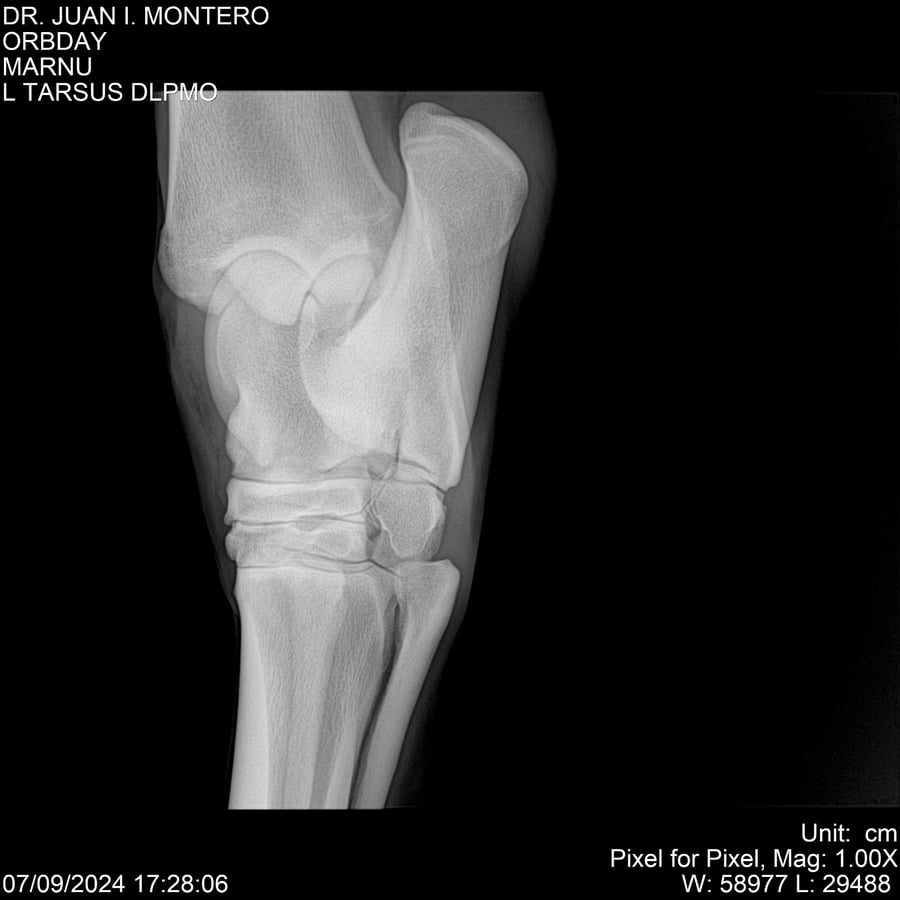

• Empresa: Abelenda N. R., Walter Hugo